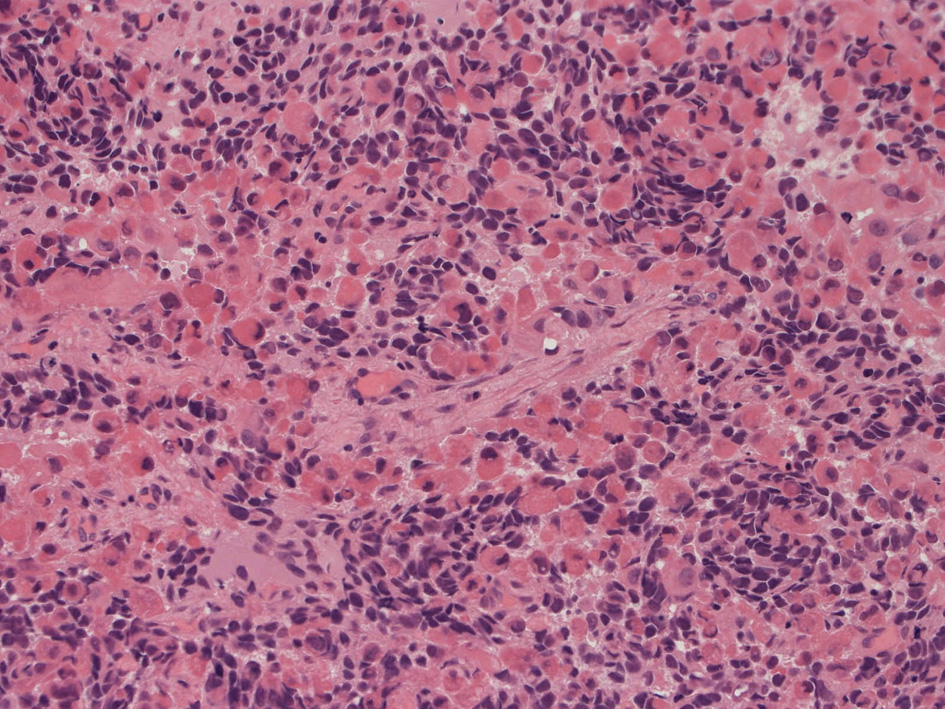

Alveolar rhabdomyosarcoma

Alveolar rhabdomyosaroma

Undifferentiated small round cell tumors of the sinonasal tract

rhabdomyosarcoma 横紋筋肉腫

40歳女性 鼻粘膜腫瘤

右頸部のしこりを自覚。近医MRIで頸部多発リンパ節腫大あり当院を紹介される。右顎下, 右鎖骨上窩にも多数のリンパ節を触れる。穿刺細胞診ではcarcinoma疑い。右鼻腔, 上顎洞にも腫瘤が認められリンパ節腫大との関係を調べるために鼻腔腫瘤の生検が行われる。

病理組織所見